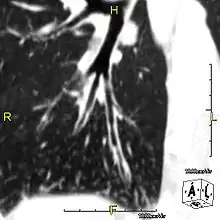

Around 80% of people with primary ciliary dyskinesia experience respiratory problems beginning within a day of birth. Many have a collapsed lobe of the lung and blood oxygen low enough to require treatment with supplemental oxygen.[1] Within the first few months of life, most develop a chronic mucus-producing cough and runny nose.[1] The main consequence of impaired ciliary function is reduced or absent mucus clearance from the lungs, and susceptibility to chronic recurrent respiratory infections, including sinusitis, bronchitis, pneumonia, and otitis media. Progressive damage to the respiratory system is common, including progressive bronchiectasis beginning in early childhood, and sinus disease (sometimes becoming severe in adults). However, diagnosis is often missed early in life despite the characteristic signs and symptoms.[2] In males, immotility of sperm can lead to infertility, although conception remains possible through the use of in vitro fertilization, there also are reported cases where sperm were able to move.[8] Trials have also shown that there is a marked reduction in fertility in females with Kartagener's syndrome due to dysfunction of the oviductal cilia.[9]

Many affected individuals experience hearing loss and show symptoms of otitis media which demonstrates variable responsiveness to the insertion of myringotomy tubes or grommets. Some patients have a poor sense of smell, which is believed to accompany high mucus production in the sinuses (although others report normal – or even acute – sensitivity to smell and taste). Clinical progression of the disease is variable, with lung transplantation required in severe cases. Susceptibility to infections can be drastically reduced by an early diagnosis. Treatment with various chest physiotherapy techniques has been observed to reduce the incidence of lung infection and to slow the progression of bronchiectasis dramatically. Aggressive treatment of sinus disease beginning at an early age is believed to slow long-term sinus damage (although this has not yet been adequately documented). Aggressive measures to enhance clearance of mucus, prevent respiratory infections, and treat bacterial superinfections have been observed to slow lung-disease progression. The predicted incidence is 1 in approximately 7500.[10]

When accompanied by the combination of situs inversus (reversal of the internal organs), chronic sinusitis, and bronchiectasis, it is known as Kartagener syndrome[3] (only 50% of primary ciliary dyskinesia cases include situs inversus).[11]